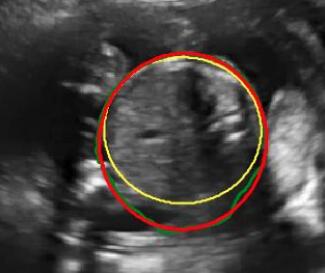

Sound-opaque occluders, including bones and calcified tissues, block the propagation of sound waves by strongly absorbing or reflecting sound waves during scanning. The regions behind these sound-opaque occluders return little to no reflections to the US transducer. Thus these areas have low intensity but very high acoustic impedance gradients at their boundaries (e.g. Fig. 1(a) left column). Reducing acoustic shadows and correct interpretation of images containing shadows rely heavily on sonographer experience. Experienced sonographers avoid shadows by moving the probe to a more preferable viewing direction during scanning or, if no shadow-free viewing direction can be found, a mental map is compounded with iterative acquisitions from different orientations.

We propose a novel method based on convolutional neural networks (CNNs) to automatically estimate pixel-wise confidence maps of acoustic shadows in 2D US images. Our method learns an initial latent space of shadow regions from images consisting of multiple anatomies and with global image-level labels (“has shadow” and “shadow-free”), e.g. Fig. 1(a). The basic latent space is then estimated by learning from fewer images of a single anatomy (fetal brain) with coarse pixel-wise shadow annotations (approximately of the images with global image-level labels), e.g. Fig. 1(b). The resulting latent space is then refined by learning shadow intensity distributions using fetal brain images so that the latent space is suitable for confidence estimation of shadow regions. By using shadow intensity information, our method can detect more shadow regions than the coarse manual segmentation, especially relatively weak shadow regions.